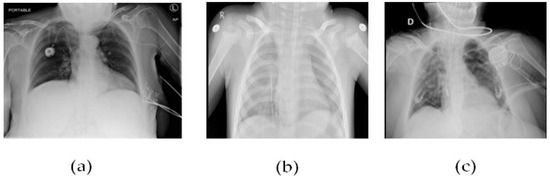

Figure 5 CT scans, or computed tomography scans, use X-rays to create detailed images of the inside of the body. CT scans can be helpful in diagnosing respiratory illnesses such as SARS-CoV-2, the virus that causes COVID-19. CT scans can show the presence of lung abnormalities such as ground-glass opacities and consolidation, which can be indicative of viral pneumonia.

Figure 5. (a) Patient healthy image, (b) Patient with pneumonia, and (c) Patient with +Ve COVID-19 images COVID-19 negative.